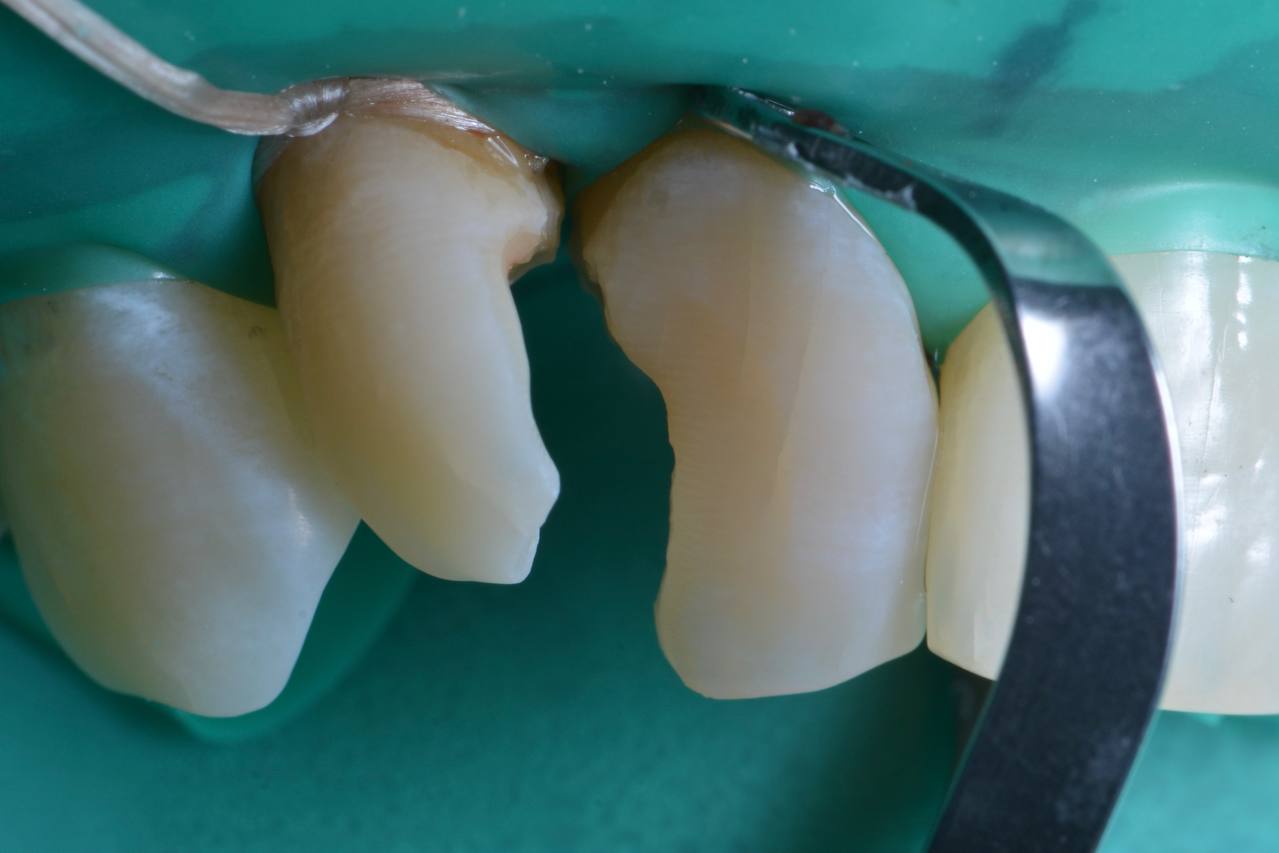

В детстве я упал и сломал передний зуб. Тогда мне сделали пломбу. Уже после ортодонтического лечения была проведена реставрация этого зуба. Теперь я очень доволен результатом работы! Спасибо!

Обратилась с проблемой эстетики переднего зуба - старая пломба пожелтела. Александр Сергеевич сделал реставрацию зуба. Очень довольна результатом!

Очень хотела убрать скол между зубами и мечтала о красивой улыбке. Реставрация спасла меня. Благодарю клинику и Егора Ивановича за проделанную работу!